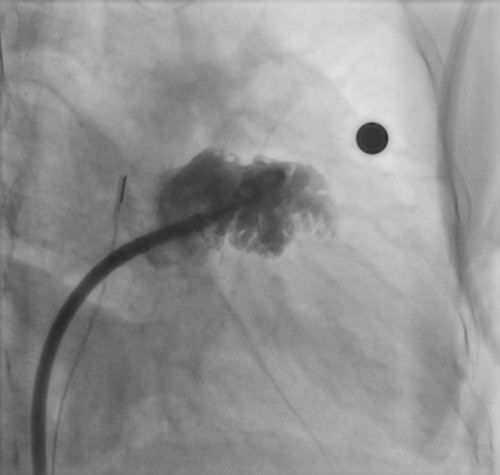

三维心腔内超声指导下成功植入封堵器